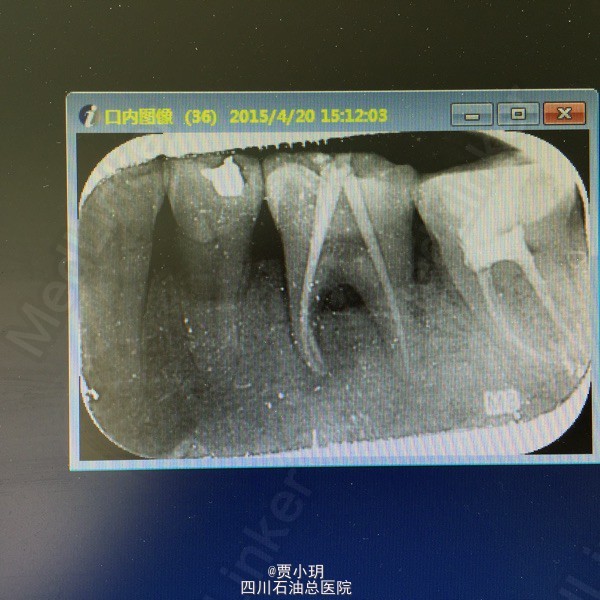

诊断:36牙周牙髓联合病变 处理:1、局麻下,行36开髓,封失活剂。同期行36牙周治疗,包括牙周洁治,根面平整,双氧水反复冲洗并上药。 2、一周后复诊,36常规行根管治疗,行MTWO根扩。 3、一周后复诊,36再次行牙周刮治,冲洗,上药。 4、一周后复诊,36行根充,复合树脂充填。观察随访,择期行牙冠修复。